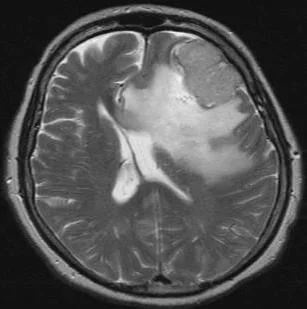

Un méningiome peut être diagnostiqué au scanner où il apparaît comme une masse ronde à la périphérie du cerveau, avec un épaississement de l’os au niveau de sa base d’insertion sur la méninge.

Il est plus fréquemment retrouvé sur une IRM sous forme d’une masse “blanche” après injection du produit de contraste intraveineux et entourée d’un œdème. Les méningiomes peuvent se rencontrer dans différentes localisations intra-crâniennes, plus ou moins facilement accessibles et qui conditionneront la technicité et les risques du geste qui vous sera proposé par votre chirurgien.

du rocher droit